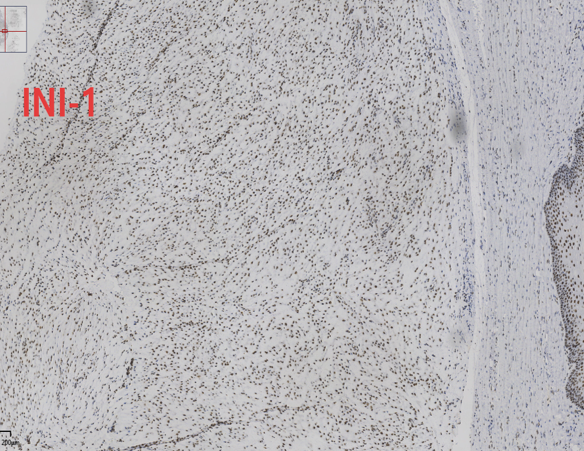

免疫组化结果:CK7(-)、CK5/6(-)、P63(-)、PAX-8(-)、Ki-67(+,约2%+)、INI-1(+,未突变)、SMA(+)、Des(+)、CD34(-)、S-100(-)、ER(+)、CK(-)、ALK(-)